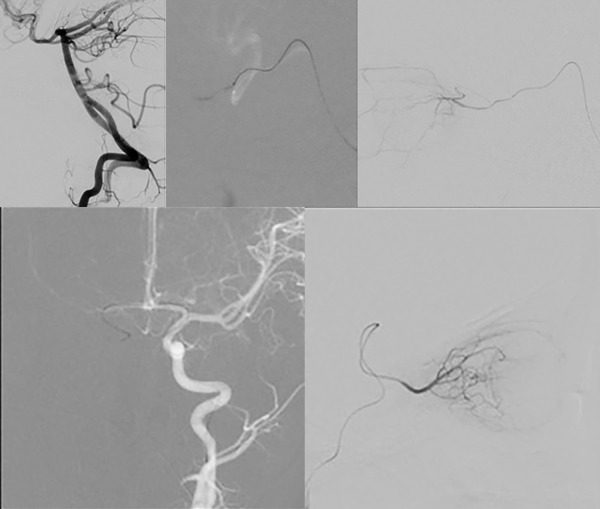

Caso clínico: Caso 1: Paciente de 4 años con antecedente de enucleación del ojo derecho. Se detectó un retinoblastoma clase D en el ojo izquierdo y se decidió tratamiento. La cateterización de la AO con un microcatéter de 1.5F y microguía de 0.012 pulgadas fue dificultoso debido al ángulo entre ésta y la ACI. Al realizar el estudio de la arteria vertebral evidenciamos una buena patencia de la arteria comunicante posterior (ACoP) ipsilateral, por lo que decidimos navegar a través de ella hasta el ostium de la AO, logrando su cateterización exitosa debido al ángulo formado. Se administró Melfalán durante 30 minutos.

Caso 2: Paciente de 1 año, con diagnostico de retinoblastoma clase D en el ojo derecho, en el cual se decidió tratamiento. Se intentó cateterizar la AO con un microcatéter de 1.5F y microguía de 0.012 pulgadas, sin embargo fue muy dificultoso por el ángulo entre la AO y la ACI. Al realizar la angiografía por el sistema vértebro-basilar no evidenciamos una ACoP patente. El estudio de la ACI contralateral mostró una arteria comunicante anterior (ACoA) permeable, por lo que decidimos navegar a través de ella. El ángulo entre la AO y la carótida permitió su cateterización y la colocación de la punta del microcatéter en el ostium de la AO. Posteriormente, se administró Melfalán y Topotecán de manera manual durante un periodo de 30 minutos.